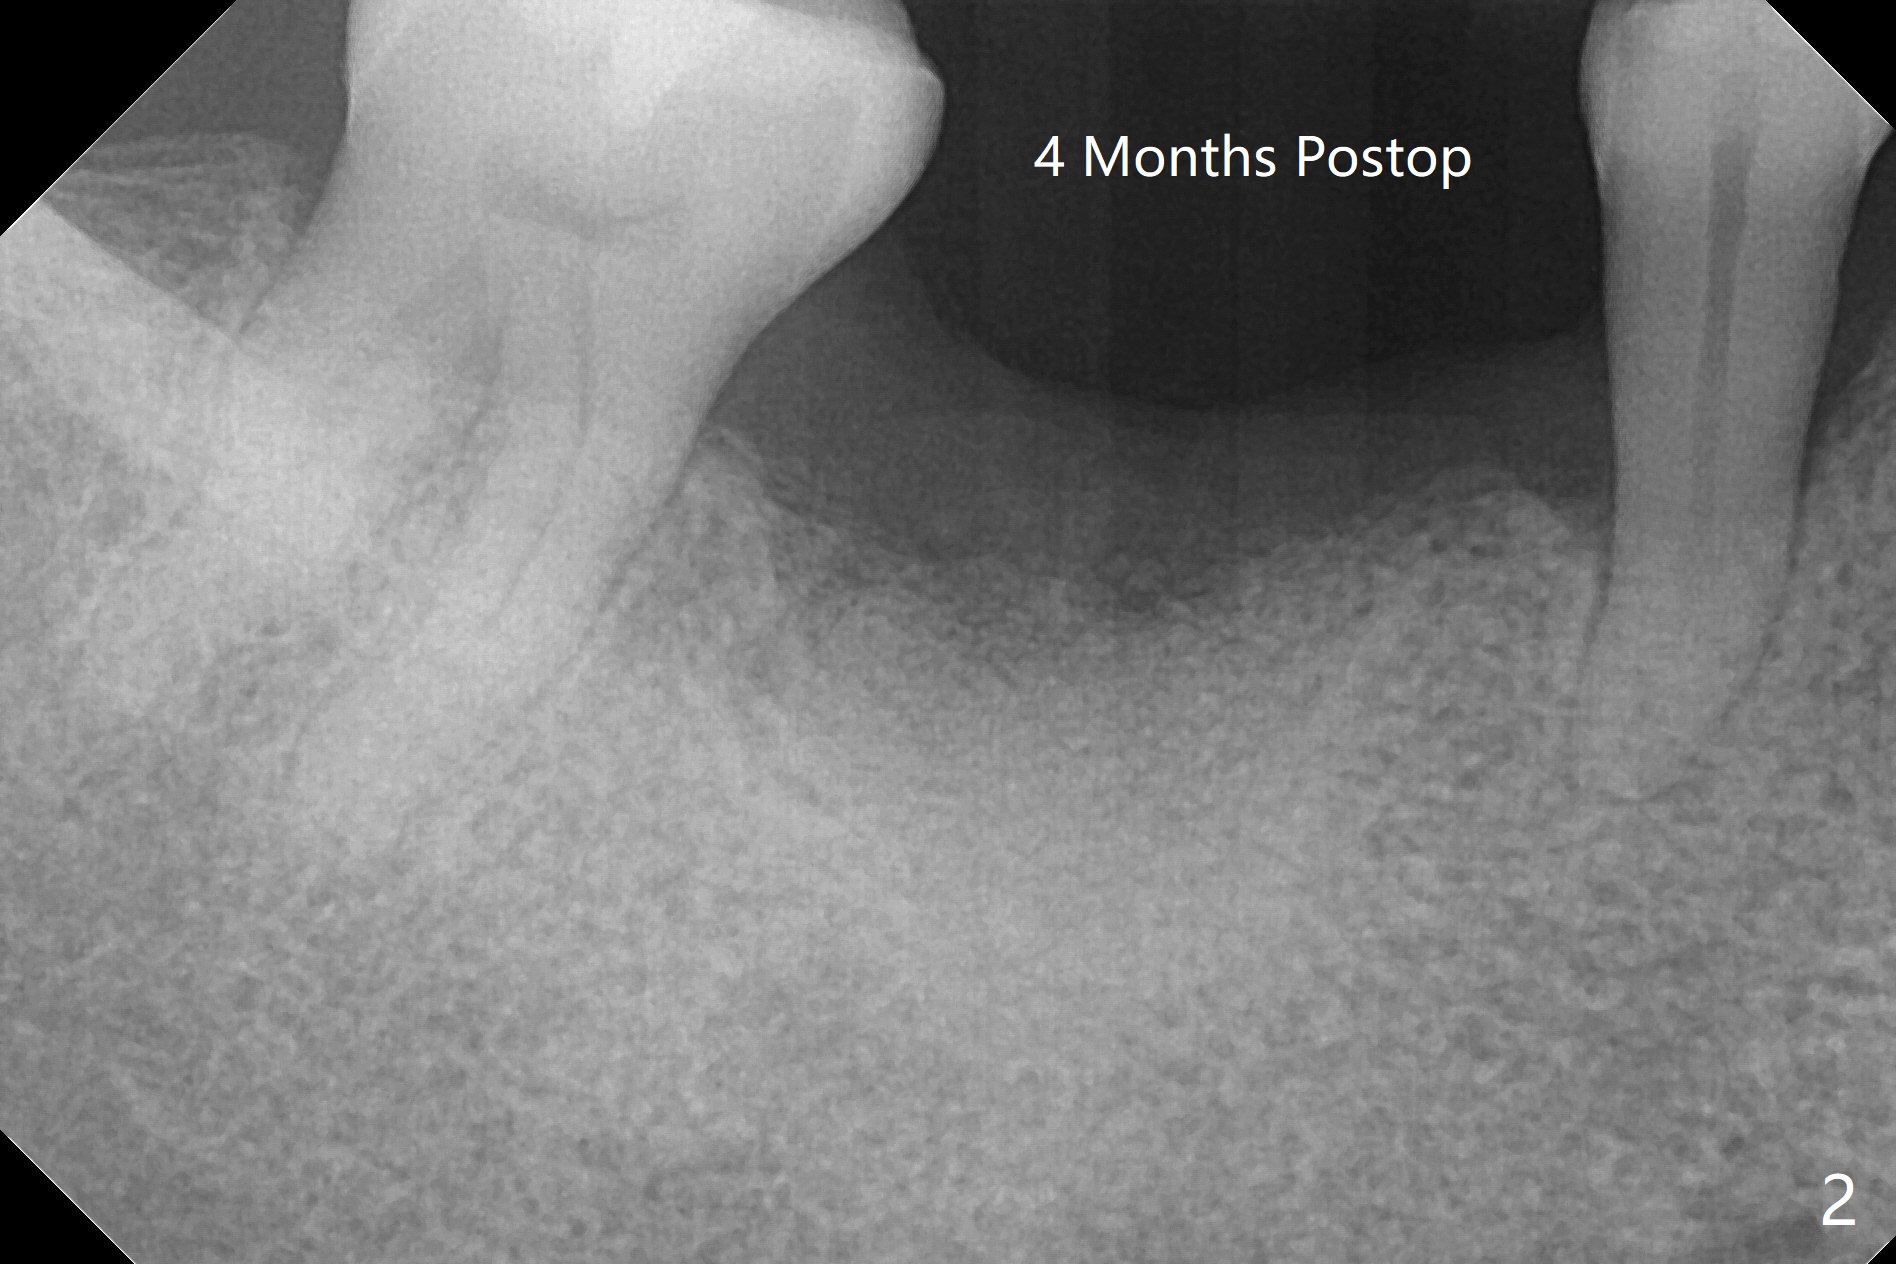

即刻植牙对害怕病人有一个好处,快速结束治疗,安慰病人可是一个麻烦事。即刻种植也可以发生于拔除失败植体之后。今天拔除的失败植牙不知厂家,基台螺丝刀对不上号,所以当植体取出时,病人和我都筋疲力尽,临时决定不做即刻种植。但是出现一个问题,事先准备粘性骨块不够,形成粘性骨块后的上清液不再形成粘性骨块,虽然仍然含有血小板,这样松散的骨粉如果放在牙槽窝上端比较容易丢失。我们解决方法是先把不粘稠的骨粉放在底层(图一:N),把粘性骨块放在上面(S),之后放置PRF膜以及不可吸收膜,使用PTFE缝线和牙周敷料。术后疼痛严重,创伤大。术后4个月牙槽嵴中央塌陷(图二)。不过还能植入5x10毫米植体(图三,四)。Return to Armaments No Deviation Xin Wei, DDS, PhD, MS 1st edition 09/15/2020, last revision 04/06/2021